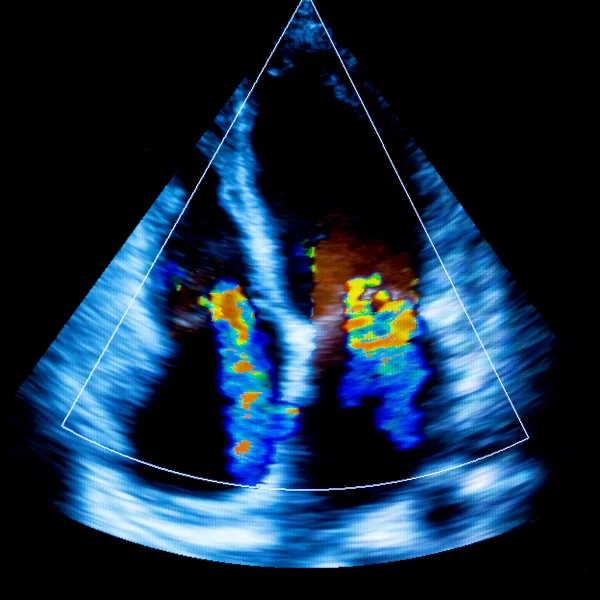

Echokardiografia dopplerowska – poziom średniozaawansowany

Ultrasonograficzna ocena serca dla średniozaawansowanych

Echokardiografia dopplerowska – podstawy fizyczne i guzikologia (wykład)